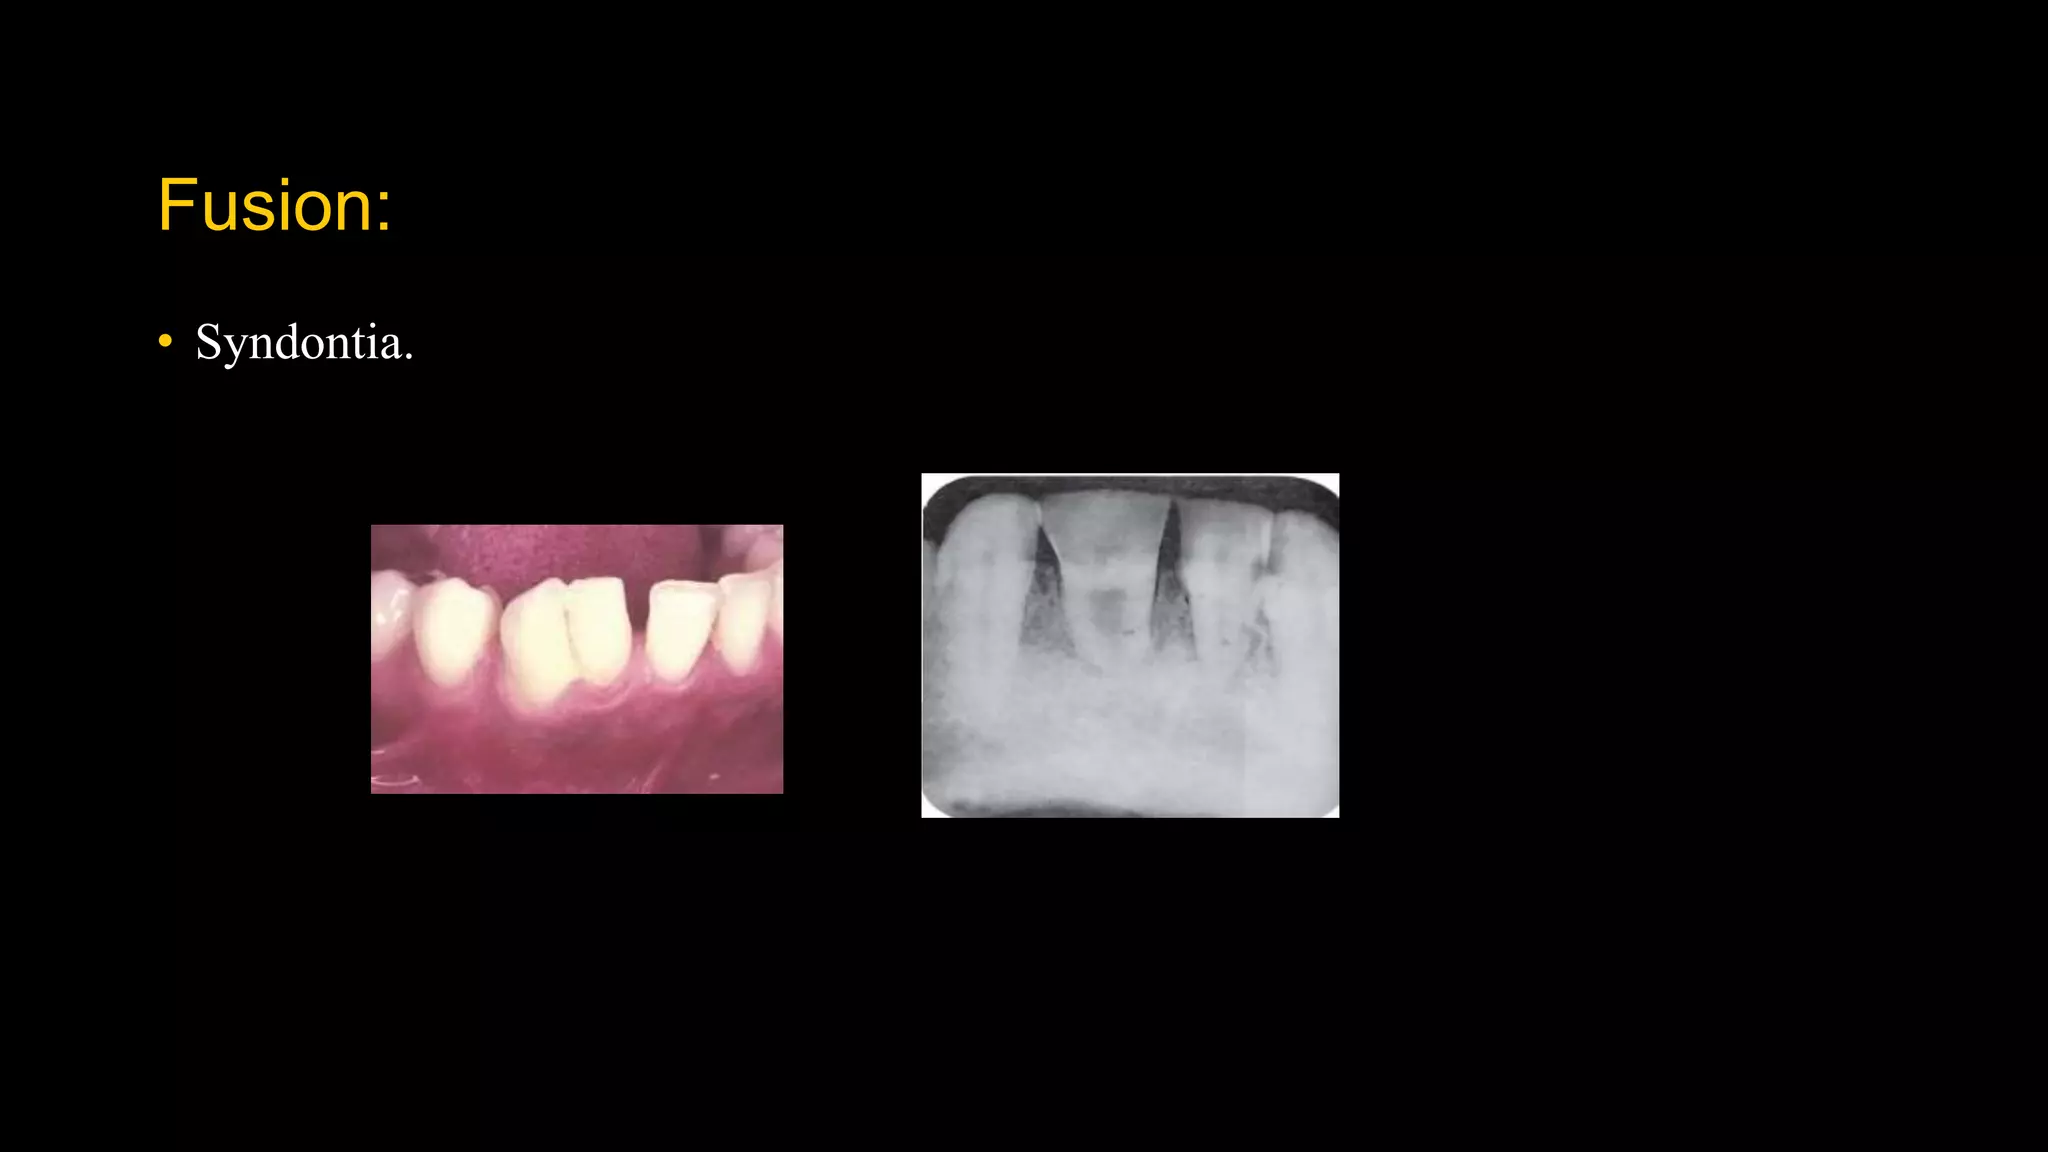

Fusion:

• Syndontia.

Frequency of occurrence:

• Anterior teeth of primary and permanent dentition.

d/d:

• Gemination.

• Macrodontia.